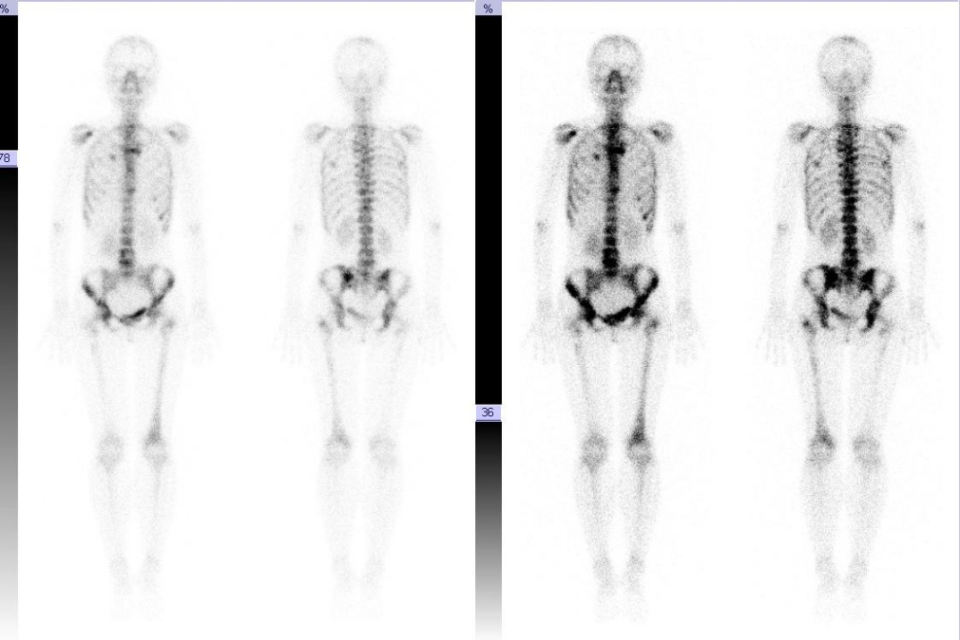

• 骨扫描:胸骨、双侧肩胛下角、多根多处肋骨、脊柱多处、骨盆、左侧股骨多发骨转移征象。临床无骨痛等发生。

图片

图 6 骨扫描